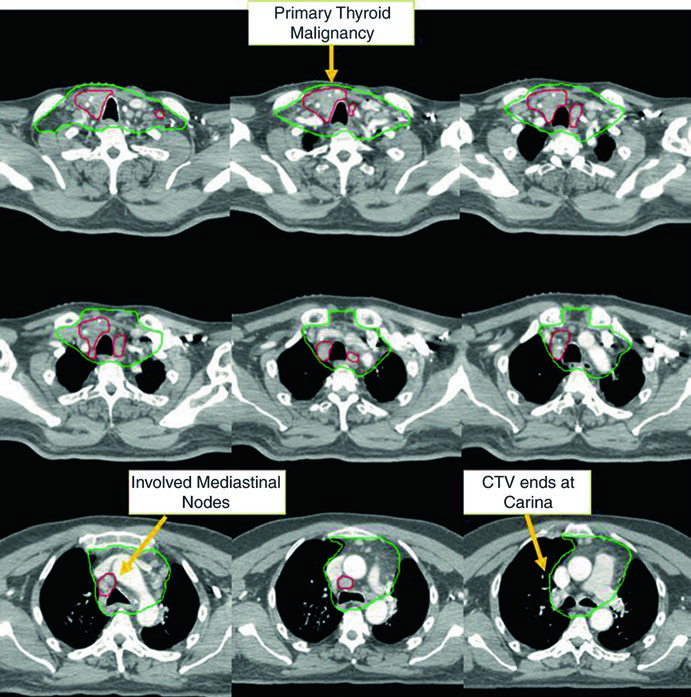

Caso 1 — Carcinoma papilar metastático (Fig. 9.1): Homem de 58 anos com carcinoma papilar metastático de tireoide, submetido a múltiplas ressecções prévias, que se apresentou com recorrência local irressecável e múltiplos linfonodos mediastinais. Recebeu quimiorradioterapia definitiva para prevenir progressão local. O CTV70 Gy (vermelho) abrange a recorrência local e linfonodos mediastinais envolvidos, enquanto o CTV60 Gy (verde) cobre as regiões subclínicas de risco. Este caso exemplifica o cenário de doença recorrente que esgotou as opções cirúrgicas — a radioterapia com dose definitiva é a melhor alternativa para controle local.

Caso 2 — Carcinoma anaplásico irressecável (Fig. 9.2): Mulher de 73 anos com carcinoma anaplásico de tireoide invadindo laringe, traqueia e esôfago. Recebeu quimiorradioterapia definitiva com doxorrubicina concomitante. O CTV70 Gy (vermelho) engloba toda a doença volumosa, e o CTV60 Gy (verde) abrange o risco subclínico. Detalhe importante: o manúbrio, que normalmente não é incluído no volume de risco, foi englobado neste caso específico por conta da doença volumosa anterior agressiva no pescoço. Essa decisão é atípica e deve ser individualizada — não se trata de protocolo, mas de resposta a uma apresentação clínica particular.

Esses dois casos ilustram a versatilidade da IMRT com dose-painting: o plano entrega simultaneamente 70 Gy ao volume de alto risco e 60 Gy ao volume subclínico, sem necessidade de boost sequencial. A escolha de doxorrubicina como quimioterápico concomitante no anaplásico reflete a agressividade dessa histologia e a necessidade de sensibilização ao tratamento, embora as opções sistêmicas tenham evoluído significativamente nos últimos anos.